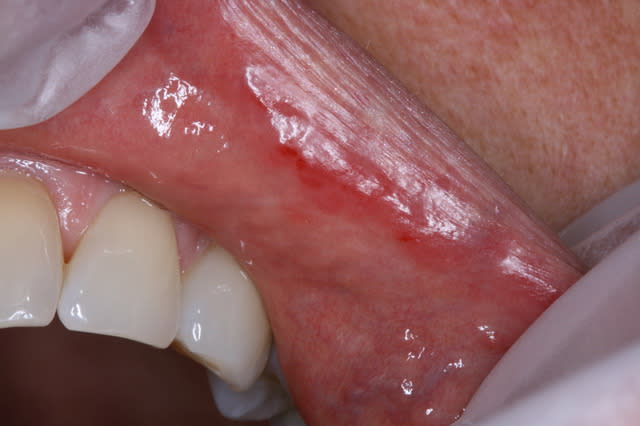

Patiente mi-cinquantaine , prend anti-hypertenseur (amilodipine et apo-hydro) ainsi que supplément calcium et vit D..

Depuis une semaine sens rugeux bout de la langue et intérieurs des lèvres. Dit avoir plus de salive (flot salivaire augmenté)

Rougeur intérieur des lèvres

rien en périphérie peau vermillon de la lèvre, seulement muqueuse interne